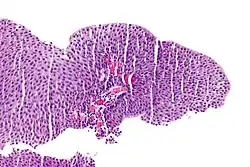

Rak urotelialny pęcherza moczowego, widoczne gniazda komórek nowotworowych

Rak urotelialny pęcherza moczowego

Inwazyjny (naciekający) rak urotelialny jest definiowany jako obecność inwazji nowotworowej poniżej błony podstawnej urotelium[74]. Makroskopowo inwazyjne nowotwory urotelialne mogą przyjmować formę brodawkowatą, polipowatą, guzkową, litą, tworzyć rozlany naciek ściany pęcherza moczowego. Zmiany mogą występować pojedynczo lub wieloogniskowo[75]. Typowo większość guzów pT1 jest brodawczakowata o niskim lub wysokim stopniu złośliwości histologicznej, z kolei guzy o większym zaawansowaniu pT2–T4 wykazują morfologię niebrodawczakowatą i cechują się wysokim stopniem złośliwości[76][77].

Mikroskopowo w utkaniu obecne są komórki tworzące gniazda, sznury komórek lub pojedyncze komórki pooddzielane desmoplastycznym podścieliskiem[76][78]. Możliwy jest bardziej rozlany wzór wzrostu nowotworu, w którym komórki tworzą arkusze, przy czym również w takim utkaniu spotyka się ogniskowo występujące gniazda komórek[78]. Komórki cechują się umiarkowaną do obfitej ilością amfofilnej lub eozynofilnej cytoplazmy i dużym hiperchromatycznym jądrem komórkowym. Jądra komórkowe wykazują znaczną pleomorficzność, nieregularne, kanciaste granice. Liczba i wygląd jąderek wykazuje znaczną zmienność. Gniazda komórek nowotworowych zwykle indukują reakcję desmoplastyczną podścieliska. Obecne są liczne figury mitotyczne i możliwa jest obecność nieprawidłowych figur mitotycznych. W podścielisku większości guzów jest obecny naciek limfocytów i komórek plazmatycznych, naciek najczęściej jest wyrażony ogniskowo od łagodnego do umiarkowanego stopnia, ale może być nasilony i rozlany[76][78]. Może być widoczna inwazja naczyń[78].